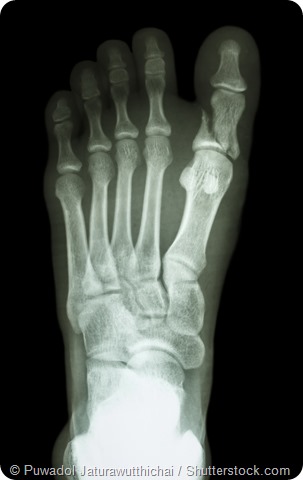

Fractured foot x-ray

X-ray showing fracture of proximal phalange at first toe

• Fractures: broken or cracked bones in the feet can be very painful.